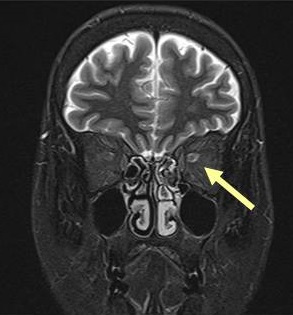

IgG4関連眼症のMRI所見は、T2強調画像で涙腺炎に加え、

- 視神経周囲組織の炎症(IgG4 眼症は視神経炎を伴う場合がある)

- 様々な眼組織に腫瘤(眼球裏面に索状の腫瘤など)

- 三叉神経(眼窩上神経と眼窩下神経)の腫大[Ophthalmic Plast Reconstr Surg. 2019 Mar/Apr;35(2):170-176.]

を認める点が、甲状腺眼症・バセドウ病眼症と異なります。造影MRIでは、いずれも増強されます。

- 下垂体・下垂体茎が腫大するため、MRIにて下垂体腫瘍と鑑別しにくいことがある